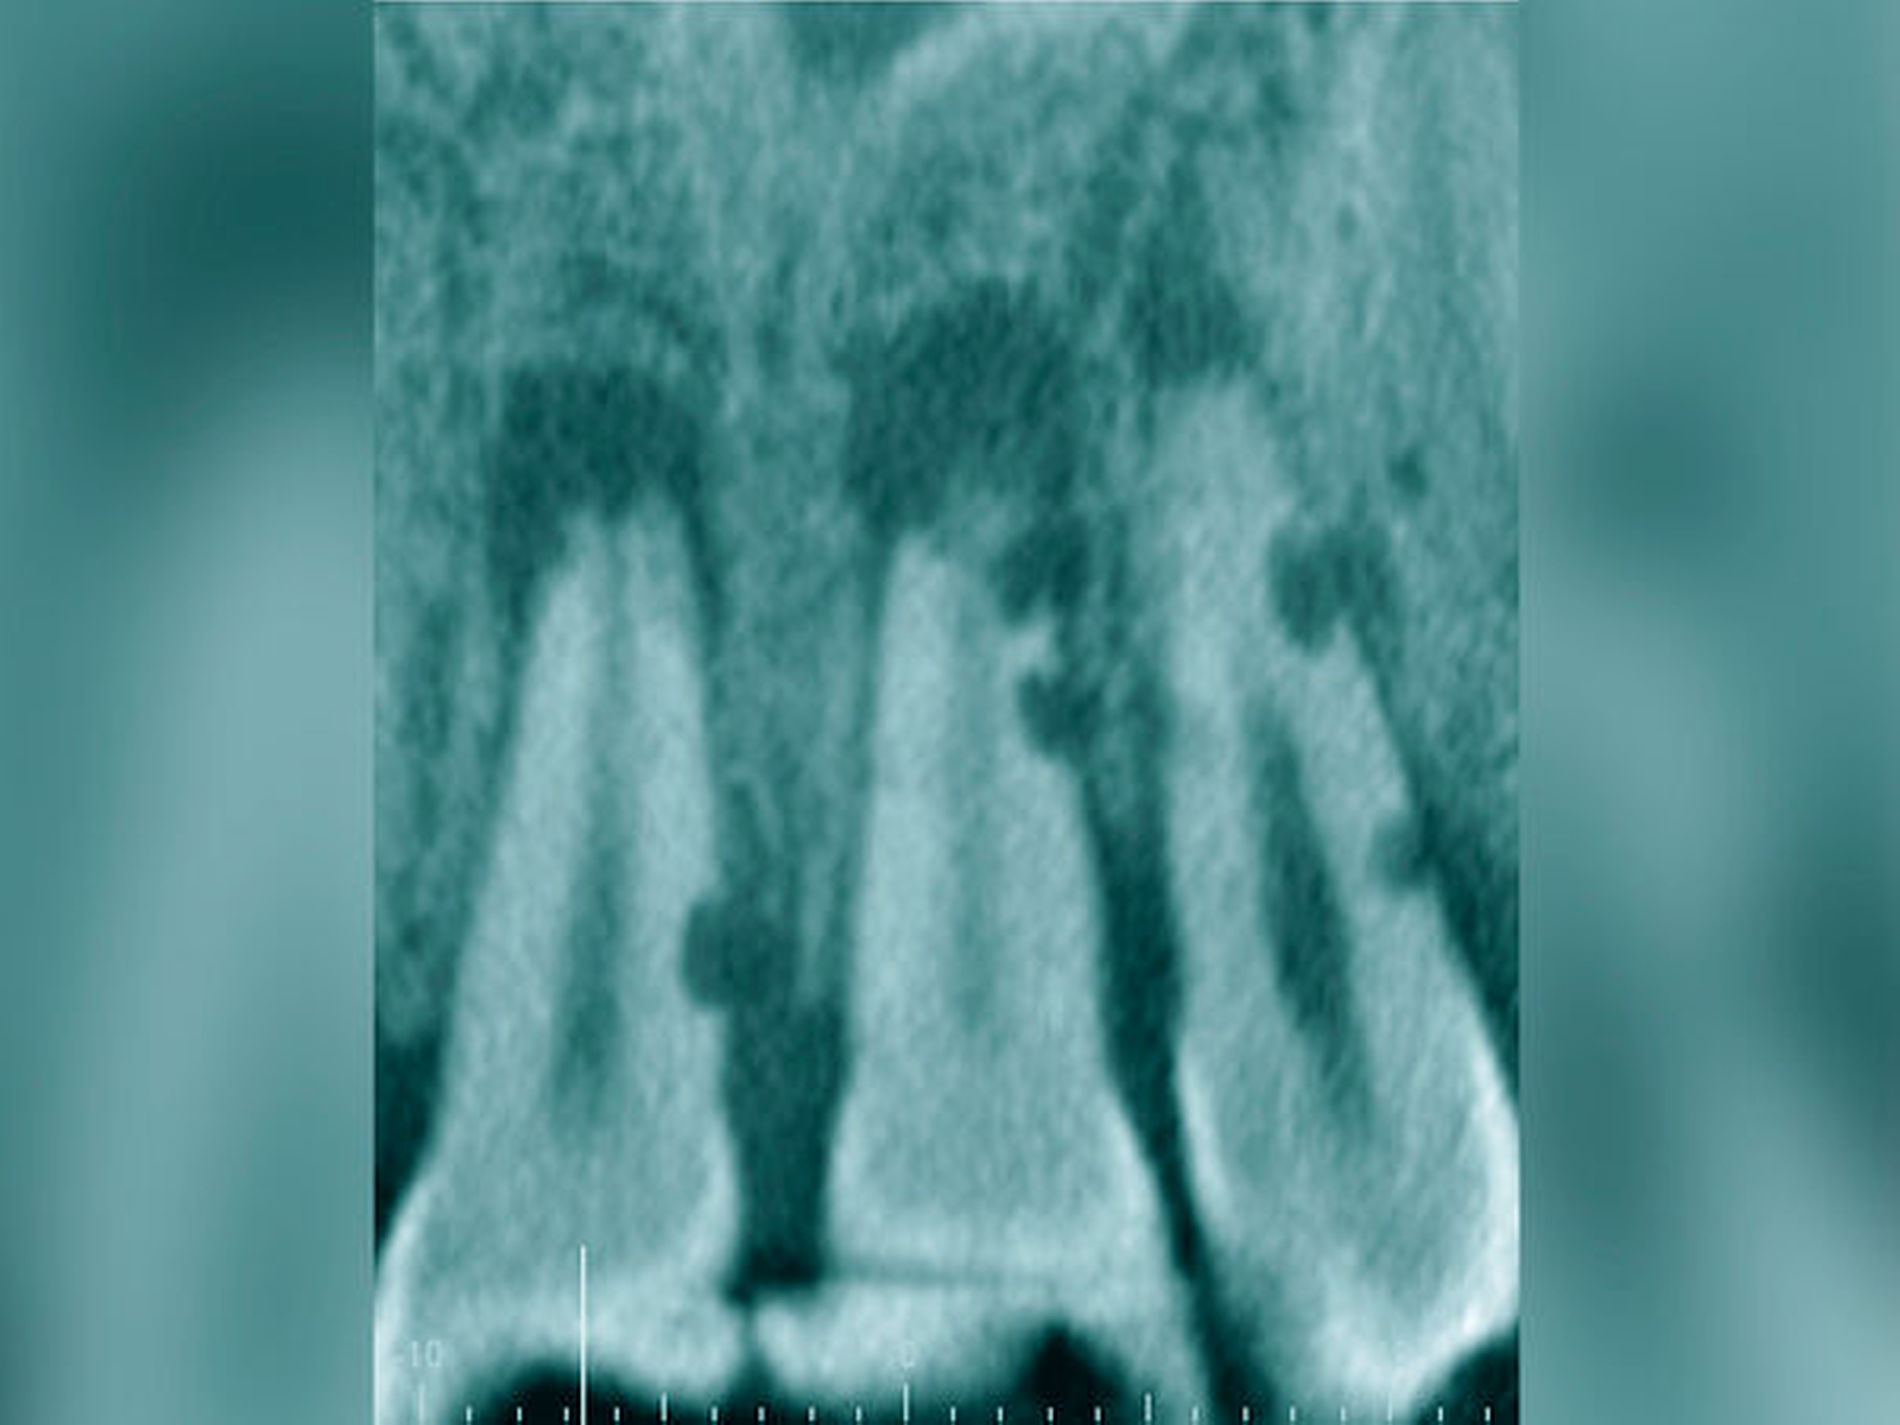

Röntgenbilder können genutzt werden, den anatomischen Schwierigkeitsgrad zu ermitteln. Lässt sich ein Wurzelkanal vollständig bis zum Apex mit einem Krümmungswinkel bis zu 30 Grad und einem großen gleichmäßigen Krümmungsradius erkennen, ist keine erhöhte Schwierigkeit in der Therapie zu erwarten (Abbildungen 1 und 2).

Krümmungsradius: Ist demgegenüber der Verlauf des Wurzelkanals unterbrochen, kann meist mit einer tiefen Wurzelkanalaufteilung gerechnet werden (Abbildung 3) [Reuver, 2002].

Lässt sich der Wurzelkanal auf der Röntgenaufnahme nur apikal erkennen, liegt meist eine Kalzifikation der Pulpa vor, die häufig erst unter Nutzung einer optischen Vergrößerung überwunden werden kann [Kiefner et al., 2017].